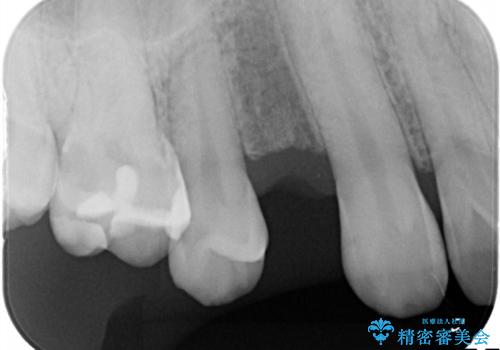

残せなくなってしまった乳歯 インプラントによる補綴